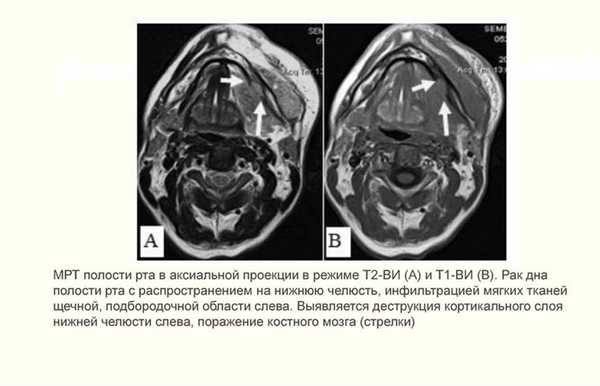

Рак полости рта

Злокачественное новообразование представляет собой длительно незаживающую язву эпителиального слоя слизистой оболочки рта и ретромолярной области.